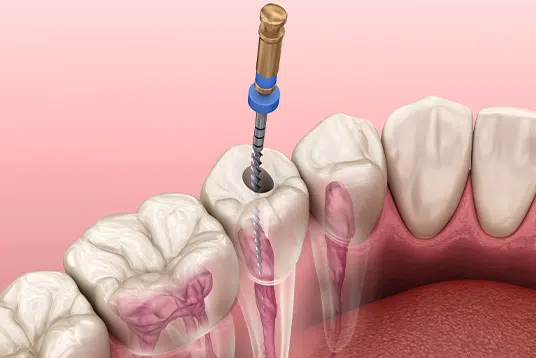

Leczenie kanałowe jest jednym z najważniejszych zabiegów w stomatologii, mającym na celu uratowanie zęba, który w przeciwnym razie musiałby zostać usunięty.

Dzięki nowoczesnym technikom i doświadczeniu naszych lekarzy specjalistów w Centrum Stomatologii Kompleksowej Aldent, możemy skutecznie leczyć zęby wcześniej skazane na ekstrakcję.

Wykorzystujemy zaawansowane metody, takie jak udrażnianie zobliterowanych (niedrożnych) kanałów, ponowne leczenie endodontyczne oraz usuwanie wypełnień, metalowych wkładów i złamanych narzędzi kanałowych pod mikroskopem.

Wszystkie zabiegi endodontyczne w naszej klinice wykonujemy z użyciem stomatologicznego mikroskopu operacyjnego, który może zapewnić nawet 25-krotne powiększenie obrazu!

Mikroskop ten pozwala nam na zauważenie wszystkich zachyłków i nieregularności wewnątrz kanałów, co jest kluczowe dla precyzyjnego leczenia.

Dzięki bardzo silnemu, bezcieniowemu oświetleniu wnętrze kanałów jest doskonale widoczne, co zwiększa skuteczność zabiegu i pozwala na osiągnięcie ponad 90% długoczasowego powodzenia w leczeniu.